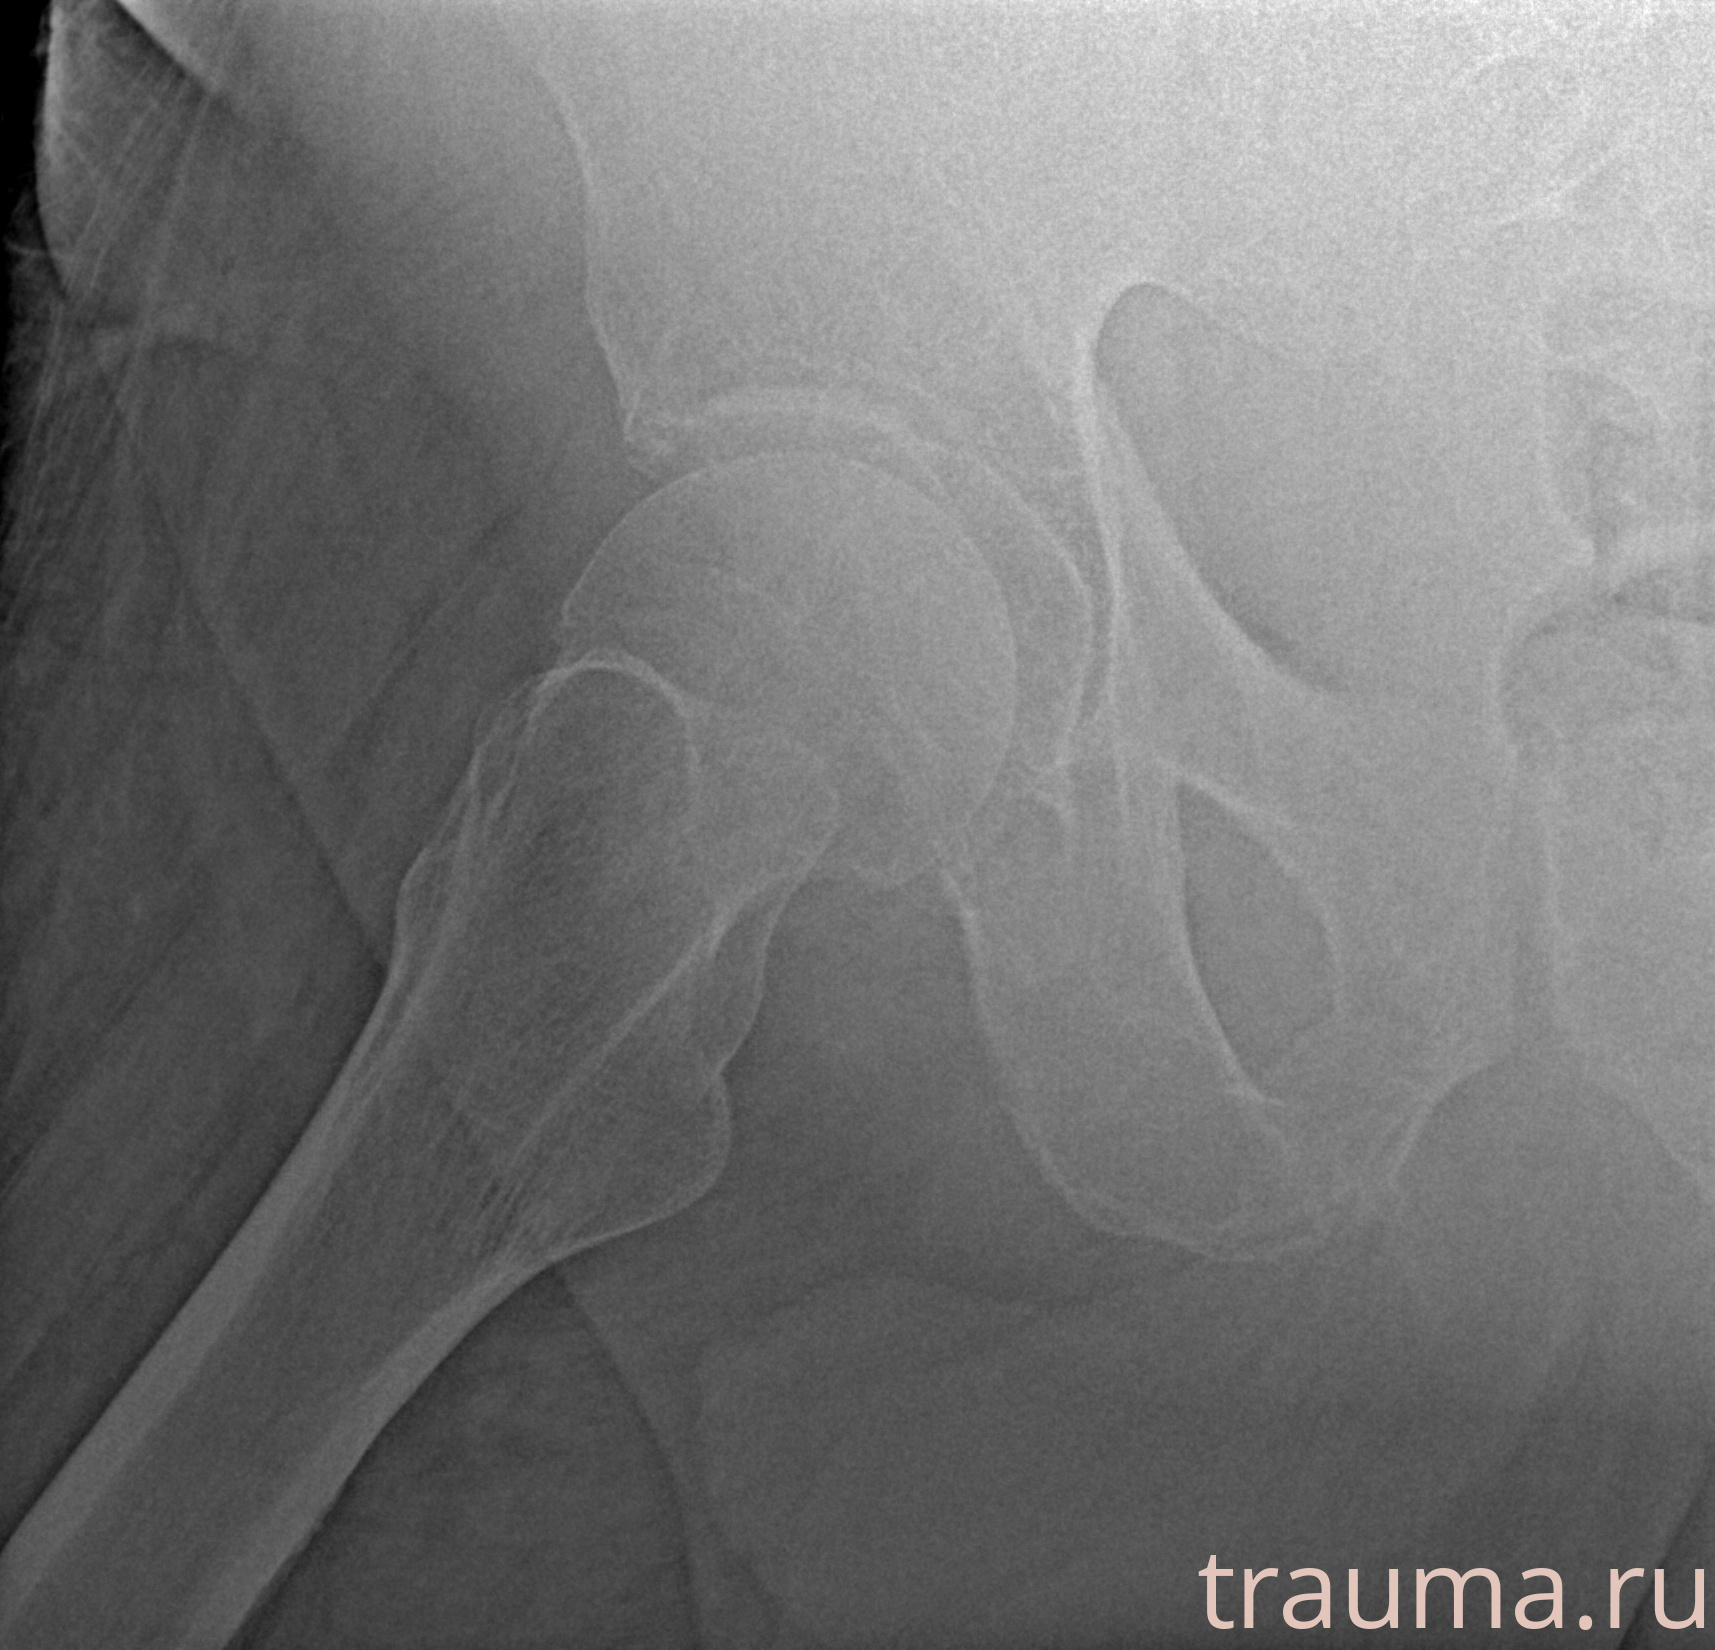

Первая помощь при переломе шейки бедра

Рентгенограммы

Рентген на дому: по вашему адресу приезжает врач-рентгенолог, травматолог-ортопед с мобильным рентгеновским аппаратом, проводит диагностику травмы или заболевания, делает необходимые рентгенограммы, дает рекомендации по дальнейшему лечению. Получить качественные снимки в домашних условиях возможно благодаря уникальной методике, разработанной МосРентген Центром для института  Склифосовского